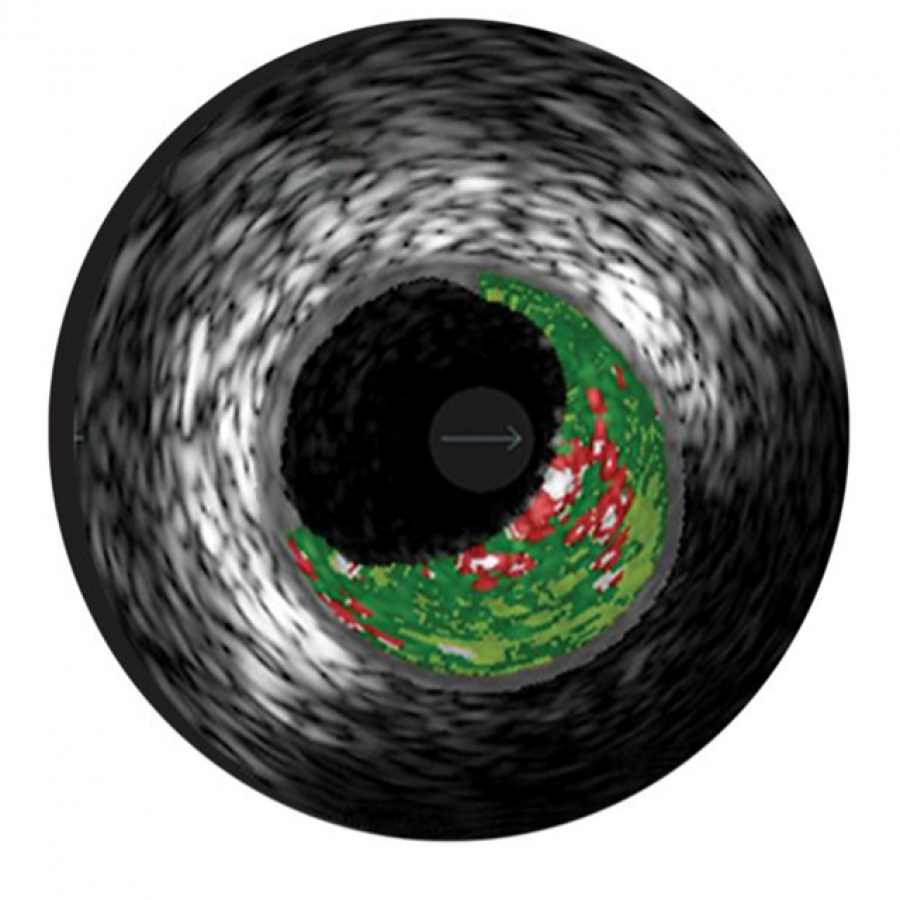

Специализированный программный режим для внутрисосудистых ультразвуковых исследований (ВСУЗИ), предназначенный для автоматизированного анализа и цветового картирования тканей стенки сосуда. Технология использует сложные алгоритмы обработки радиочастотных сигналов для дифференциации типов тканей атеросклеротической бляшки в режиме реального времени.

Изображение в режиме виртуальной гистологии VH позволяет оценить морфологию атеросклеротического поражения сосуда.